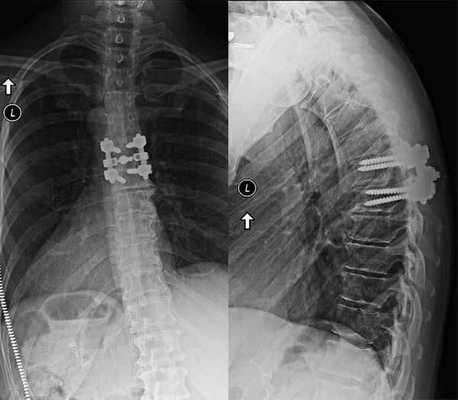

3 месяца после операции.

Пациенты, которым была проведена стабилизация поясничного отдела (моно- или многоуровневая), шейного или грудного отдела, оповещают в отзывах об определенных трудностях в процессе восстановления. Распространенная беда - это появление таких послеоперационных осложнений, как:

- поломка, смещение имплантированного стабилизатора (стержня, пластины, винтов, кейджей и т.д.);

- развитие местных воспалительных или инфекционных реакций;

- усиление болей в месте установленной конструкции;

- нарастающая мышечная слабость в руках или ногах.